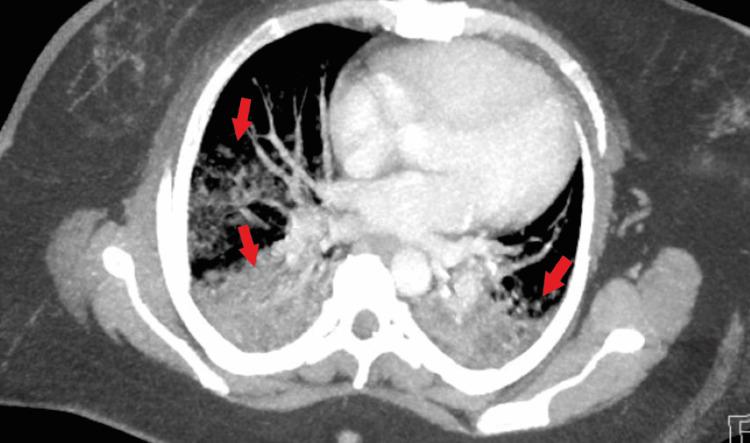

Antineutrophil cytoplasmic antibody (ANCA)-associated vasculitis is an autoimmune inflammatory disease that usually affects the small-sized vasculature, most notably of the lungs and kidneys. One of the challenges of suspecting and diagnosing the condition lies in the insidious and unclear symptoms of presentation. In this case report, we discuss the case of a patient who initially presented with solely unclear pulmonary symptoms, without other organ system dysfunction.

抗中性粒细胞胞浆抗体(ANCA)相关性血管炎是一种自身免疫性炎症性疾病,通常累及小血管,最显著的是肺部和肾脏的血管。怀疑和诊断该病的挑战之一在于其症状隐匿且不明确。在本病例报告中,我们讨论了一名患者的病例,该患者最初仅表现为不明确的肺部症状,而无其他器官系统功能障碍。